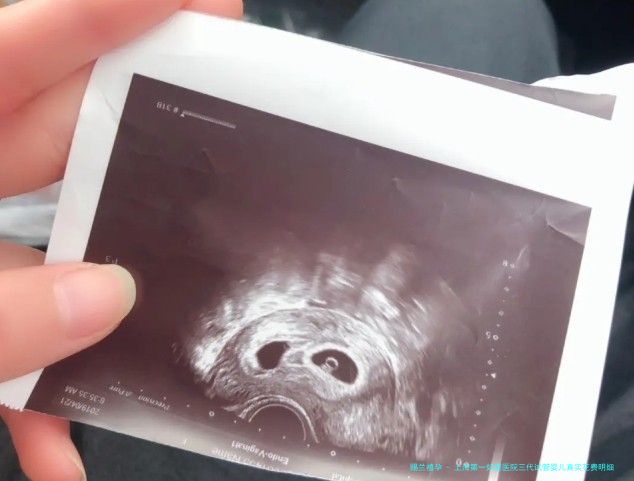

我本年32岁,成婚三个年头一向没有怀上孩子,检查后医生建议我考虑试管婴儿。据说吉尔吉斯斯坦的试管婴儿技术不错,并且费用相对稍低,我想了解一下在吉尔吉斯斯坦助孕生子的全部费用大概要几许?如若我预算18万元钱,是不是足以了呢?